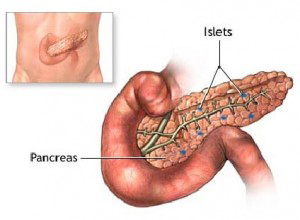

Καρκίνος Παγκρέατος

Το αδενοκαρκίνωμα του παγκρέατος παραμένει ένας από τους λιγότερο ιάσιμους νεοπλασματικούς όγκους του ανθρώπου, με την ριζική χειρουργική επέμβαση να αντιπροσωπεύει τη μόνη ρεαλιστική πιθανότητα για θεραπεία.

Δυστυχώς η πλειοψηφία των ασθενών με καρκίνο του παγκρέατος δεν μπορούν να υποβληθούν σε χειρουργική θεραπεία, λόγω της τοπικής προσβολής παρακείμενων ζωτικής σημασίας δομών όπως η άνω μεσεντέρια αρτηρία, ή λόγω ύπαρξης μεταστατικής εντόπισης.

Δυστυχώς η πλειοψηφία των ασθενών με καρκίνο του παγκρέατος δεν μπορούν να υποβληθούν σε χειρουργική θεραπεία, λόγω της τοπικής προσβολής παρακείμενων ζωτικής σημασίας δομών όπως η άνω μεσεντέρια αρτηρία, ή λόγω ύπαρξης μεταστατικής εντόπισης.